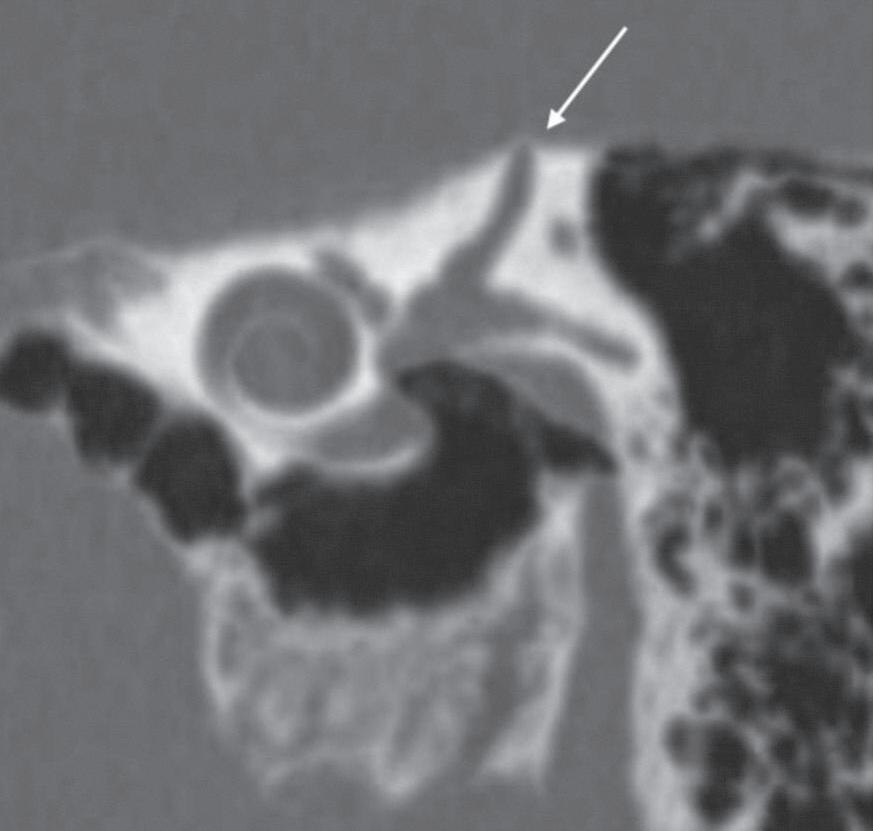

Fig. 1-7. (a, b) Histiocitose de células de Langerhans. Lesões osteolíticas frontal esquerda e nos ossos temporais. TC axial (a): axial: lesões focais osteolíticas bem definidas na porção escamosa dos ossos temporais, mais extensa à esquerda (setas).

1-8. Malformação da orelha externa. Microtia (seta em a), atresia do conduto auditivo externo (CAE), placa óssea atrésica (b).

1-9. Malformação das orelhas externas e média. Atresia óssea bilateral. (a) TC coronal bilateral: placas ósseas atrésicas (setas) e cavidades timpânicas rudimentares. (b) Reconstrução 3D de TC visão lateral: CAE não individualizados, placa óssea atrésica (setas).